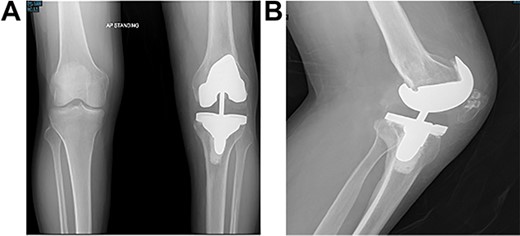

At the 2-year follow-up visit, the patient’s active ROM continued to be between 4 and 85° (Fig. 7). Patient’s functional outcome score was measured using the Knee Injury and Osteoarthritis Outcome Score pre- and post-operatively, with marked improvement in scores noted from 45 to 76%.

Post-operative plain radiographs at 2-year follow-up visit; (A) 2-year post-operative AP radiograph showing implant in place with decreased lateral gap sized to be 1.57; (B) 2-year post-operative lateral radiograph of the knee showing implant in a satisfactory position.